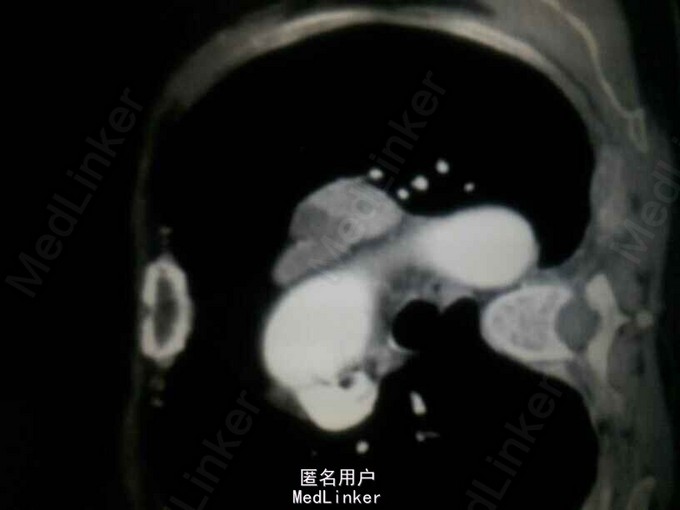

入院后查钾:2.63,钙:3.72,同时尿素氮14.23,肌酐140,碱性磷酸酶672。同时B超提示双肾多发结石。即考虑甲旁亢可能。行PTH:2143。基本明确确诊甲旁亢。但查双侧甲状旁腺B超正常。胸部增强CT提示主动脉弓旁软组织肿块影,双侧多发肋骨骨质破坏。甲状旁腺显像:左胸局部放射性异常摄取。 诊断:异位甲状旁腺肿瘤,甲旁亢,高钙血症,肾结石,病理性骨折。 予降钙等治疗后行剖胸纵膈肿瘤切除术